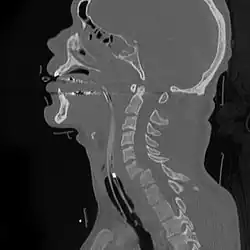

A fracture of the base of the dens (a part of C2) as seen on CT